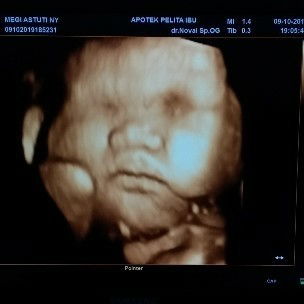

my baby girls

uk 31 week. alhamdulillh sesuai keinginan suami. babynya prempuan. cuman ya itu.. idungnya pesek amat. ga tau ikut siapa ? mngkin krna pengaruh pipi tembemnya y?? hidungnya qra" msih bisa brubah apa ga ya... ??